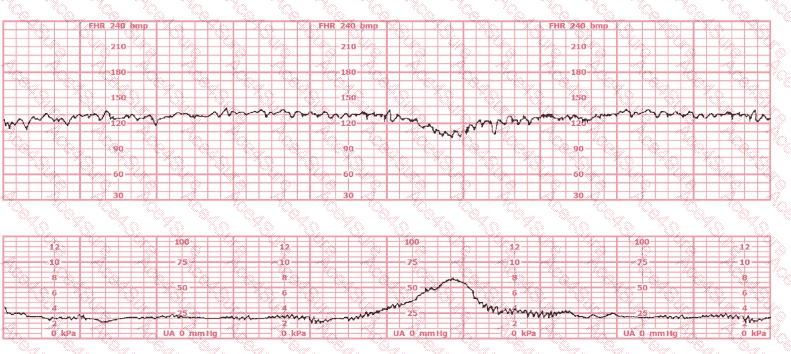

The tracing demonstrates an abrupt-onset, sharp, V-shaped deceleration, occurring simultaneously with or slightly after a contraction—classic for variable decelerations, which are caused by umbilical cord compression.

According to AWHONN Fetal Heart Monitoring Principles & Practices, variable decelerations are defined by:

“Abrupt decreases in FHR below baseline of at least 15 bpm, lasting at least 15 seconds and less than 2 minutes.”

This creates the characteristic sharp ‘V’, ‘U’, or ‘W’ shape on the monitor.

Thus, the tracing is most consistent with variable decelerations caused by umbilical cord compression.